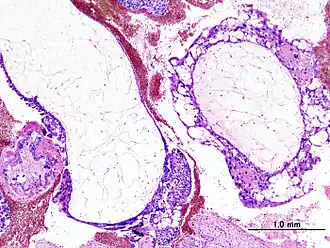

![]() Гистопатологическая картина пузырного заноса (полный тип). Окраска гематоксилином и эозином. | |